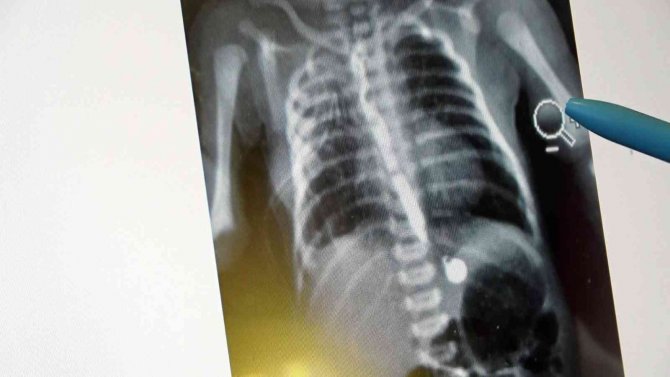

Samsun'da tıp dünyasında nadir gözüken durumlardan biri yaşandı. Murat (27) ve İlknur (26) Kaya çiftinin ilk bebekleri olan Erva Kaya, yemek borusu olmadan dünyaya geldi. Erken müdahale edilmezse sonucu ölüm olan durum karşısında aile, VM Medical Park Samsun Hastanesi'nde görev yapan Çocuk Cerrahisi Uzm. Opr. Dr. Ayşe Bahar Edirne'ye ulaştı. Uzm. Dr. Edirne, bebeğin 3 santimetre olan yemek borusunu ameliyatla 15 santimetreye çıkararak hayatını kurtardı.

Bebeğin tedavisi hakkında bilgi veren Uzm. Dr. Edirne, "Bebeğimiz doğduğunda yapılan ön tetkiklerde yemek borusunun olmadığı anlaşıldı. 2-3 günlük olduktan sonra ameliyatını gerçekleştirdik. 15 gün sonrasında da ağızdan beslemeye başladık. Yemek borusunun oluştuğunu çekilen filmlerde tetkik ettik. Sonrasında da ailesinin yanına verdik. Kontrolleri yapıldığında ise hiçbir problemi olmadığı görüldü. Eğer bu hastalık tespit edildiğinde zamanında tedavi edilmezse yemek borusu olmadığı için bebeğin beslenme şansı olmuyor. Ondan sonra da maalesef yaşama şansı olmuyor. Bu hastalık acil tedavi edilmesi gereken bir sorun. Öncelikle ultrason ve ön tetkikler yapılıyor. Bütün hazırlıklar yapıldıktan sonra özellikle yeni doğan yoğun bakımın olduğu bir donanımlı bir hastanede bakımının yapılması gerekiyor. Ameliyat da başarılı geçtiği takdirde bu şekilde doğan bebekler hayata tutunuyorlar. Ameliyat yapılmazsa yaşama şansı olmayan bir hastalıktır. Binde bir ihtimalle karşımıza çıkıyor" dedi.